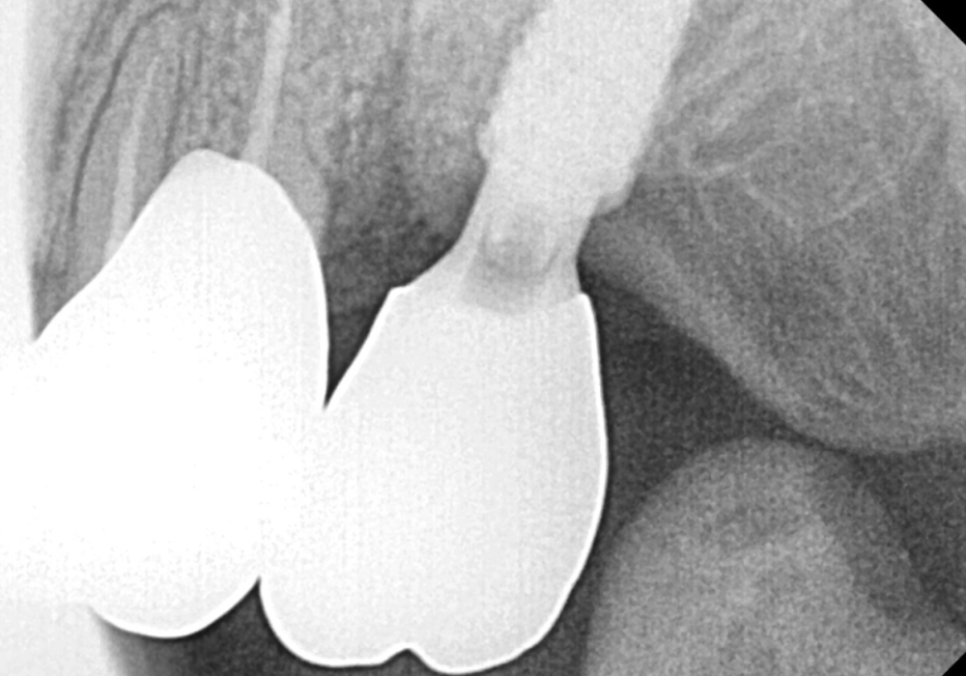

그로부터 약 5개월 뒤,

251105

안타깝게도 맨 끝 치아(#27)에

다시 통증이 느껴져

결국 고심 끝에 발치를 진행하게 되었습니다.

뽑고 난 뒤 치아를 직접 살펴보니,

사진처럼 뿌리 끝까지 수직으로

선명하게 파절된 선이 보였어요.

겉으로는 보이지 않던 깊은 곳에서

이미 치아가 완전히 갈라져 있었던 것이죠.

다행히 환자분은 만 65세가 넘으셔서

건강보험 임플란트 혜택을 받으실 수 있었는데요~

부담스러운 비용을 크게 낮추어

임플란트 수술을 진행하셨고,

260429

3개월 뒤 임플란트 기둥과 뼈가

단단히 굳은 것을 확인하여

최종 지르코니아 보철물로

아주 튼튼하게 마무리해 드렸습니다. ^^